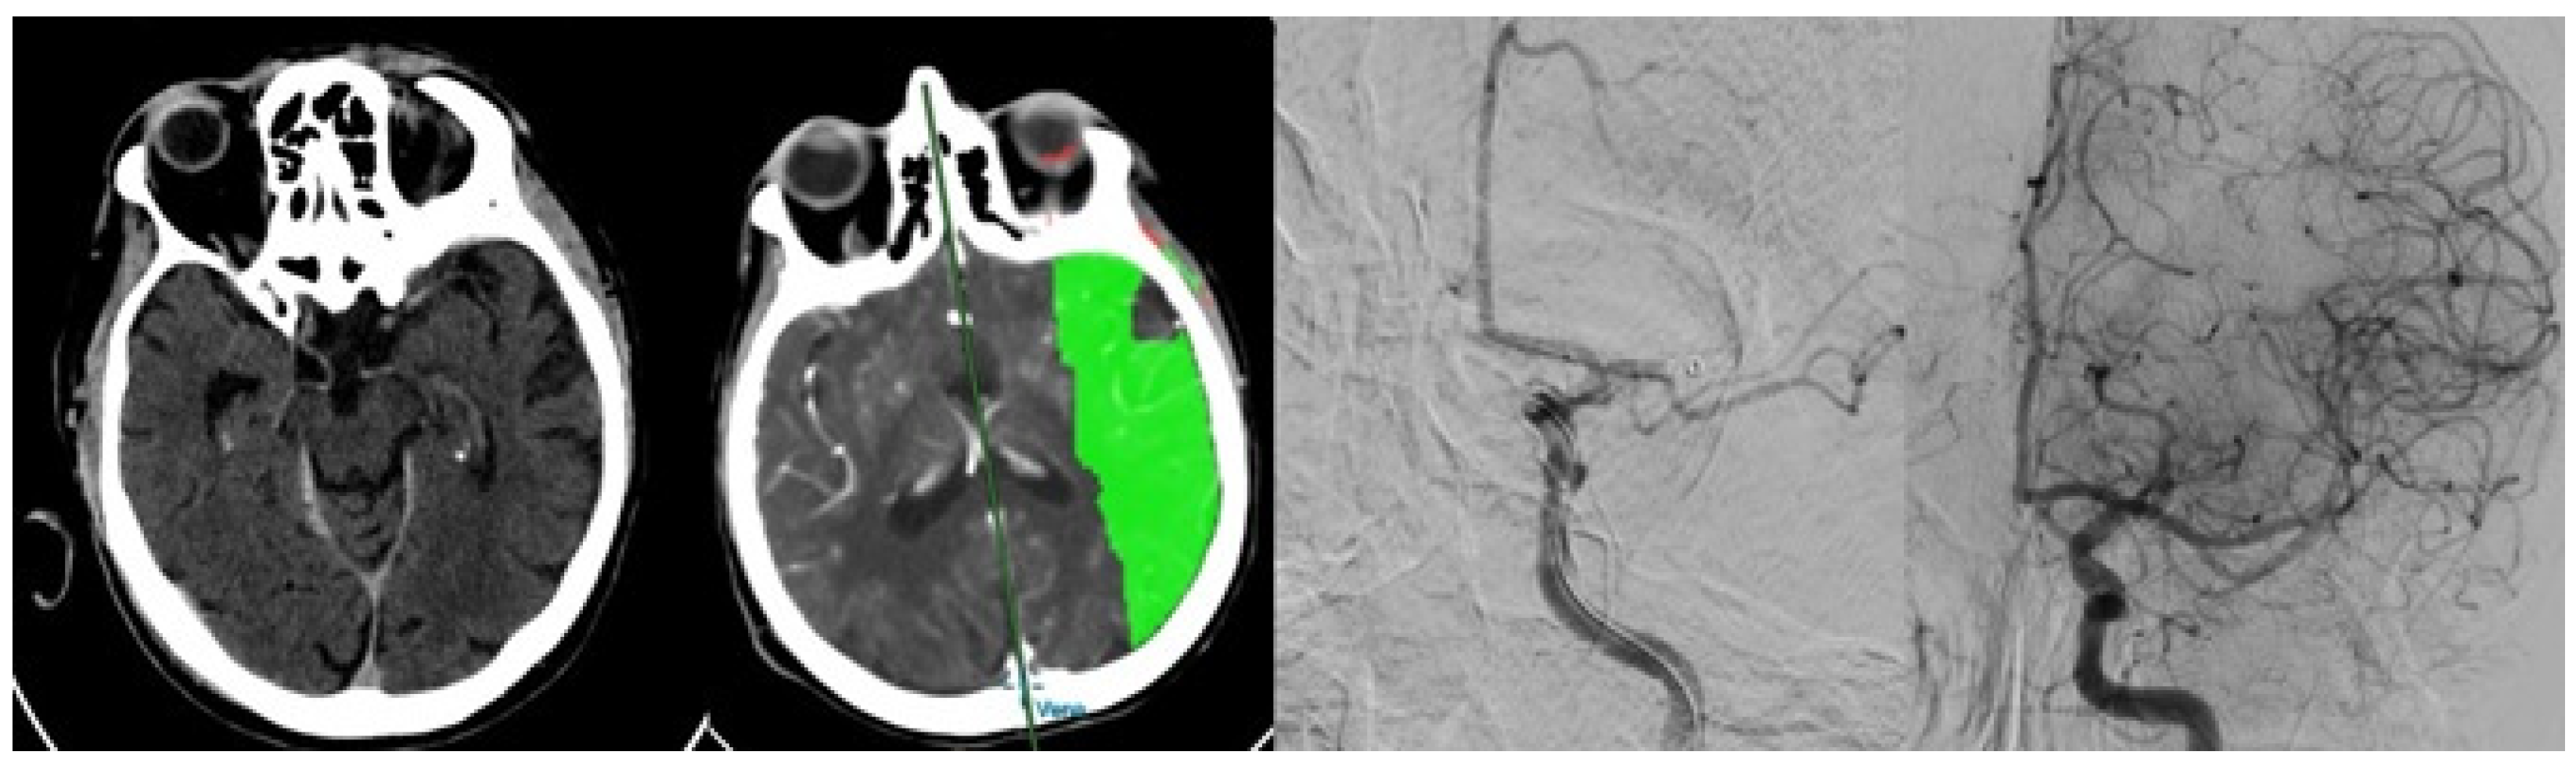

- Guzzardi, G.; Del Sette, B.; Stanca, C.; Galbiati, A.; Cernigliaro, M.; Carriero, A.; Stecco, A. Mechanical Thrombectomy by a Direct Aspiration First Pass Technique (ADAPT) in Ischemic Stroke: Results of Monocentric Study Based on Multimodal CT Patient Selection. Stroke Res. Treat. 2018, 2018, 6192483. [Google Scholar] [CrossRef]